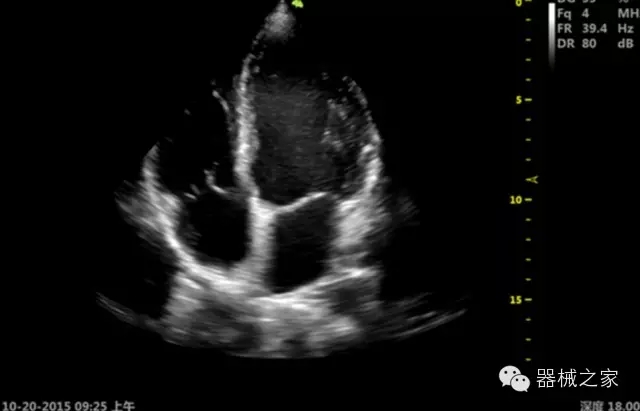

臨床圖片賞析

產(chǎn)品特點(diǎn)

·獨(dú)有的RF平臺(tái)提高微小細(xì)節(jié)顯示、圖像對(duì)比度和邊界清晰度;

·特有的XCEN探頭,超寬的帶寬,表現(xiàn)更高分辨率和對(duì)比度;

·單晶純凈波探頭提供更佳的穿透力和彩色敏感度;

·飛依諾特有心臟純凈波探頭提供更好的穿透力和彩色敏感度,以及結(jié)合TView梯形拓展改善困難病人深部組織成像;

·獨(dú)有RF敏感血流使得心臟血流完美呈現(xiàn);